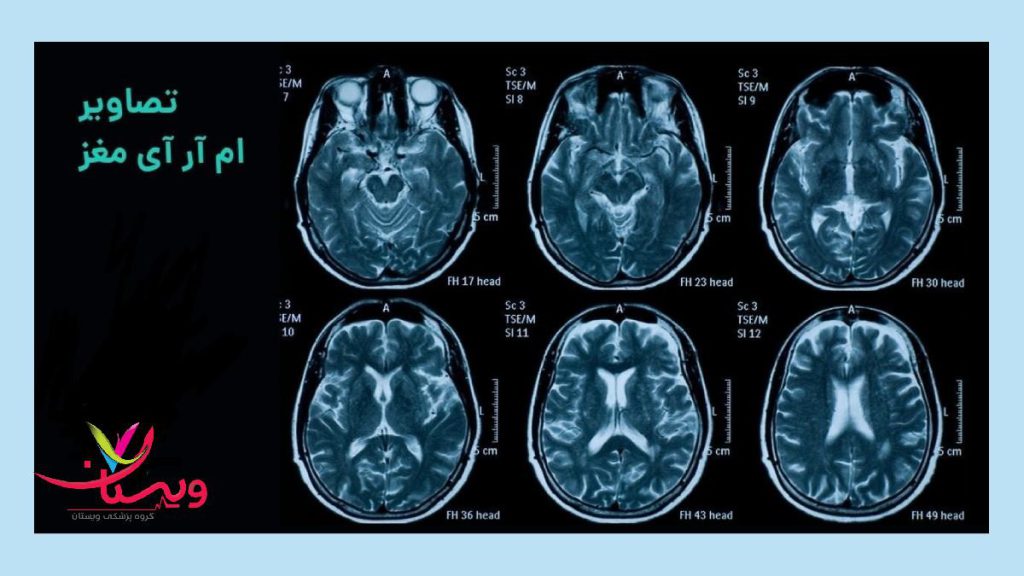

ام آر آی مغز🧠

ام آر آی مغز تصاویری دقیق از مغز و بافتهای عصبی ارائه میدهد.

ام آر آی مغز میتواند برای تشخیص و پیگیری بسیاری از بیماریها و اختلالاتی که مغز را تحت تأثیر قرار میدهند، از جمله موارد زیر استفاده شود:

ام آر آی مغز: این روش تصویربرداری غیرتهاجمی با استفاده از میدان مغناطیسی و امواج رادیویی، تصاویر دقیقی از ساختارها و بافتهای مغز ایجاد میکند. این تصاویر به پزشکان کمک میکند تا اختلالات و بیماریهای مغزی مانند تومورها، سکته مغزی و اختلالات عروقی را تشخیص دهند